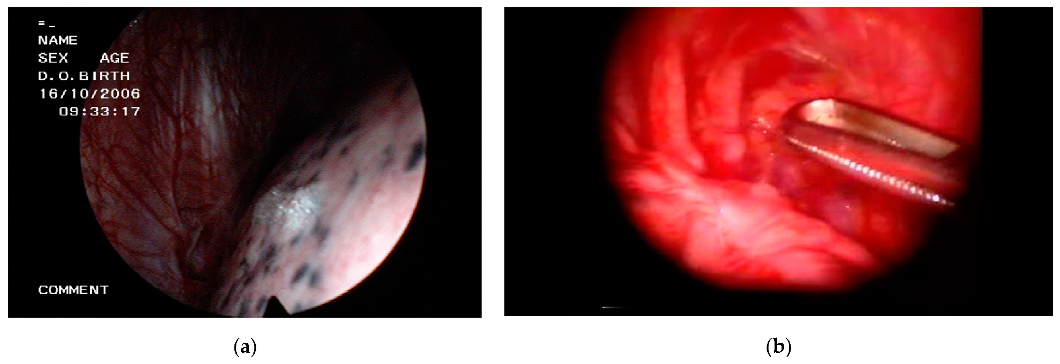

| Technical variants | Mini-thoracoscopy 3, flex-rigid thoracoscopy 4 | Uniportal 5, needlescopic 6, nonintubated |

| Indications in SP patients | Pleurodesis, electrocoagulation of blebs | Bullectomy/blebectomy, pleurodesis, staple line coverage |